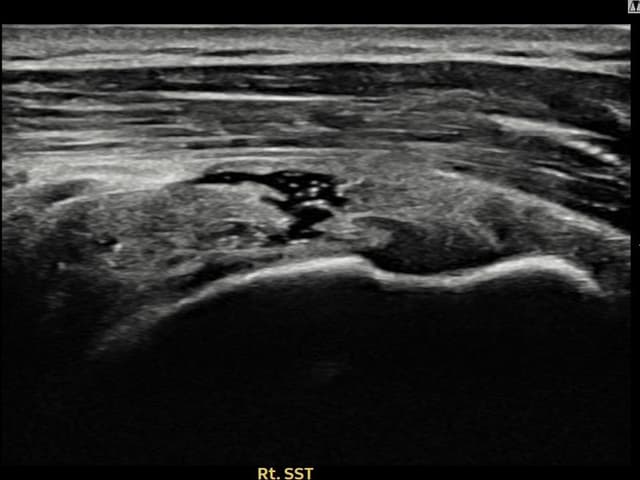

[촬영시기:23.09.01~23.11.03]

[어깨인대 축소봉합술] 우측 어깨 통증이 수개월간 지속되어 내원하셨습니다.